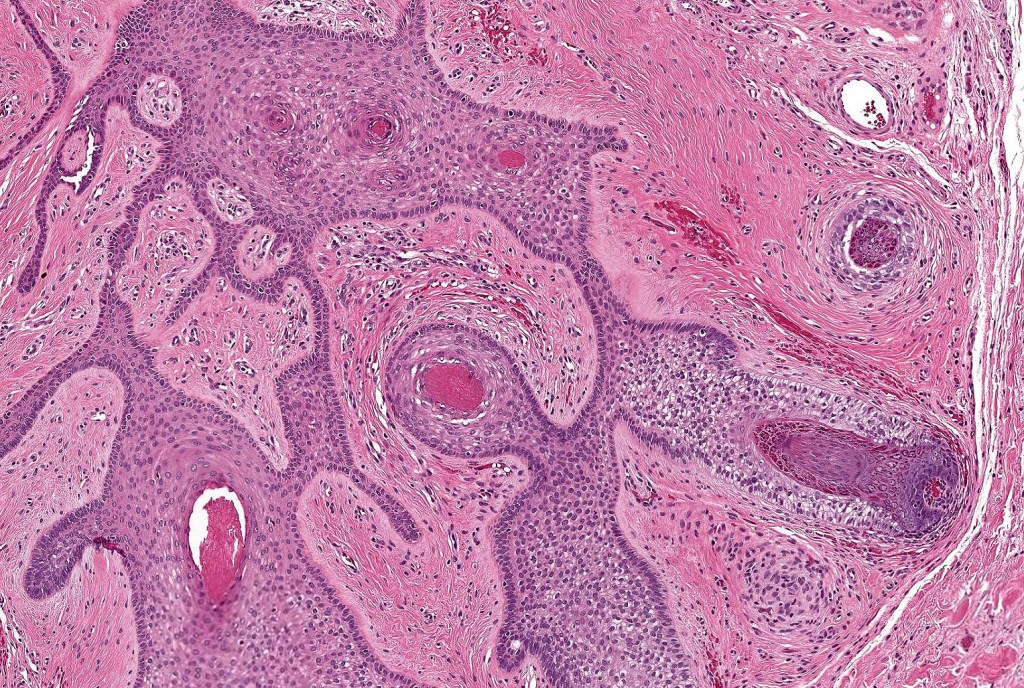

•The cyst contains keratinous debris, and its wall shows conspicuous sebaceous & sometimes hair follicular elements are also evident

•Some authors believe that this entity overlaps sebaceous trichofolliculoma

Folliculosebaceous cystic hamartoma can be distinguished from trichofolliculoma/sebaceous trichofolliculoma by the striking connective component and retraction artifact.